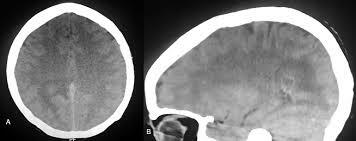

Se estaban desarrollando programas de IA para identificar los estudios de imágenes con patologías que ponen en peligro la vida, tales como hemorragias o infartos intracraneales, facilitando la priorización de esos exámenes sobre aquellos que son menos urgentes. http://www.bvs.hn/RFCM/pdf/2015/pdf/RFCMVol12-2-2015-5.pdf